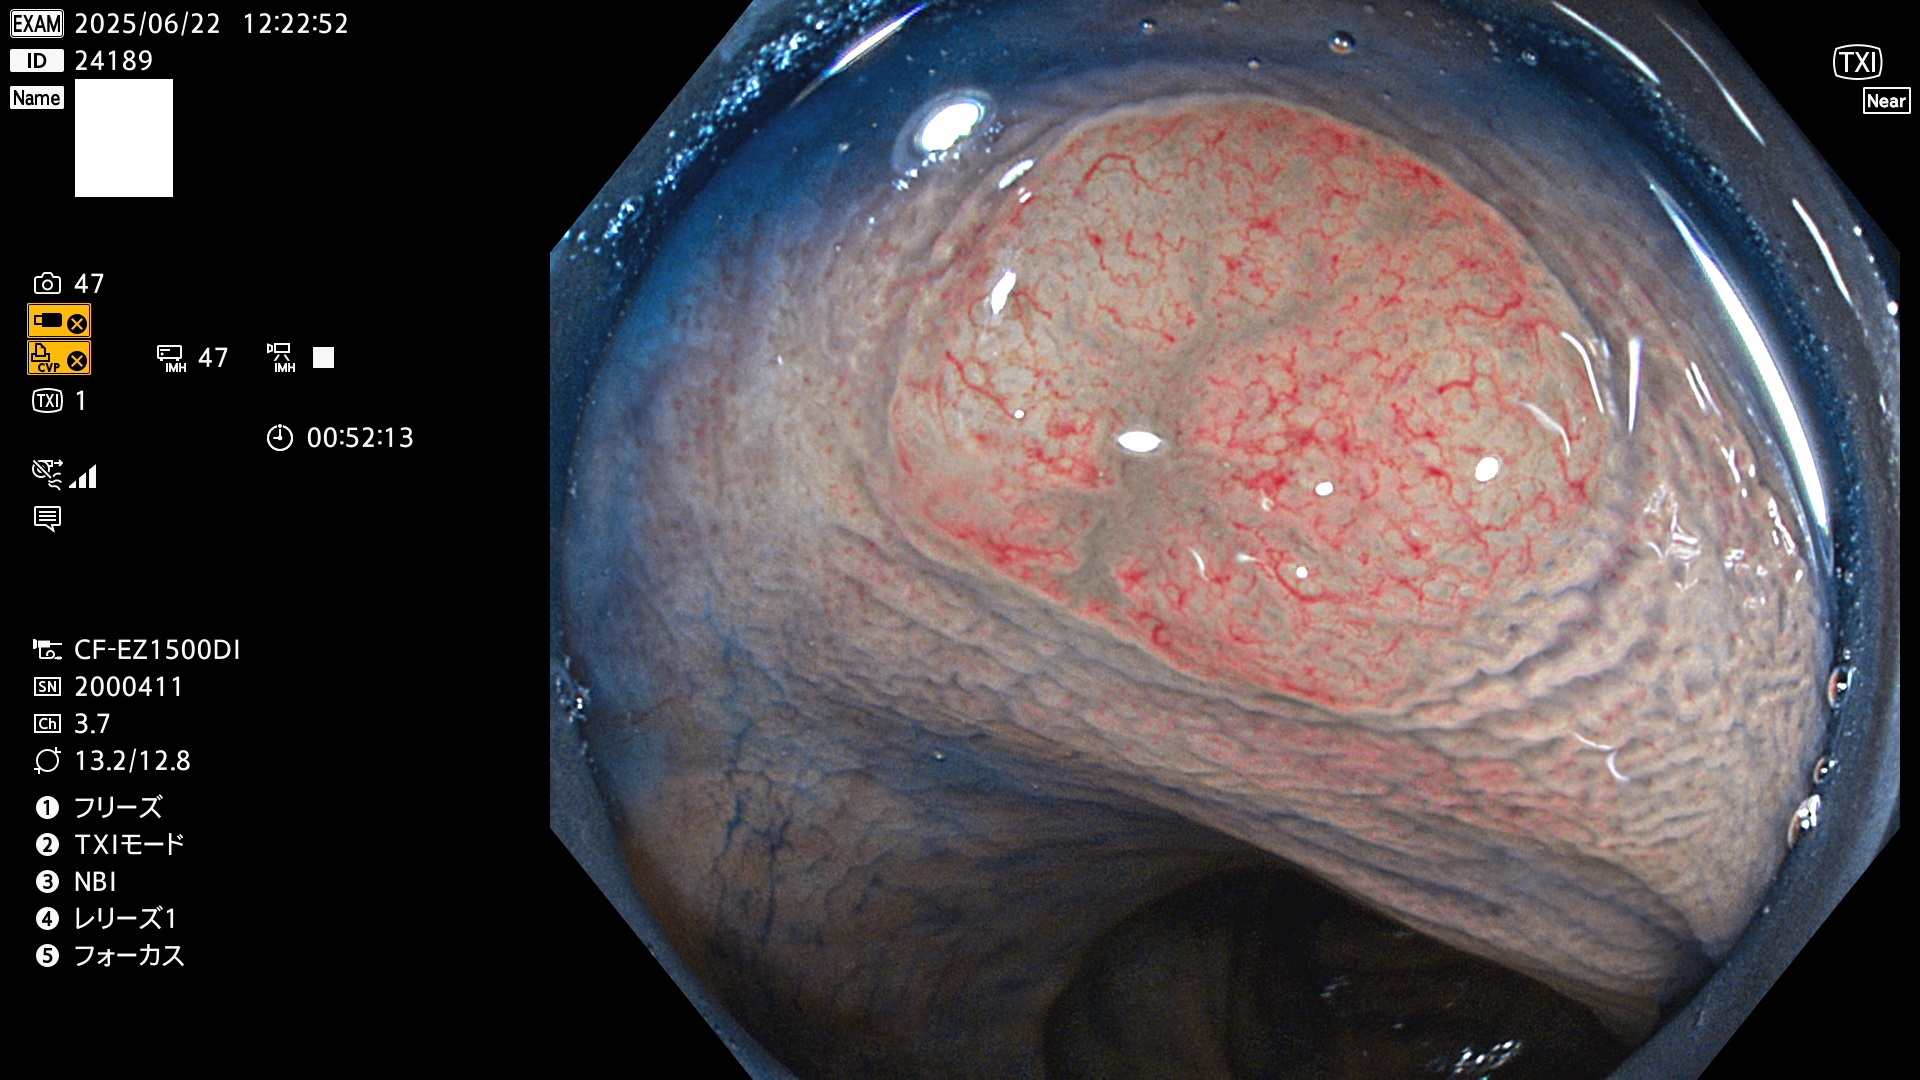

今週のUb、Uc型腺腫

完全に平坦な物をUb、陥凹している物をUcと呼びます。Ubは認識が困難で、Ucはびらん(炎症)と紛らわしいために見落とされやすく、「内視鏡後・大腸癌」の原因になります。

抽出の対象期間 2025年6月19日〜6月22日の4日間(48件の検査)10個 (10/48=20%)